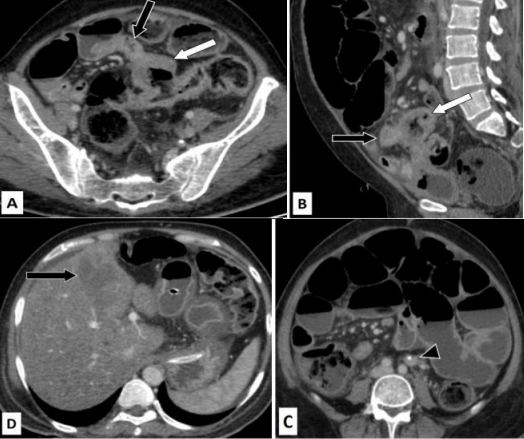

Figure 7: False positive for T4 disease and true positive for nodal involvement.

Years old male presented with abdominal pain. Ultrasound was suggestive of focal large bowel wall thickening. Colonoscopy revealed malignant growth in recto-sigmoid junction.

Figures 7A (axial CT image in venous phase) and 7B (sagittal CT image in venous phase) show concentric asymmetric wall thickening involving the sigmoid colon (white arrow) and pericolic fat stranding and extramural venous engorgement (white arrowheads). Figures 7C (sagittal CT image in venous phase) and 7D (coronal CT image in venous phase) show involvement of the pericolic fat inferior to the sigmoid colon reaching up to the superior wall of urinary bladder probably breaching the peritoneal reflection (black arrowheads). Two enlarged lymph nodes with perinodal stranding are seen in left para-aortic region (black arrows). Surgical excision of the involved segment was done. Post-operative histopathology revealed T3 tumor with nodal involvement.